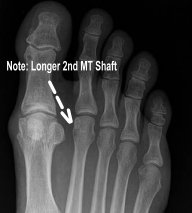

Morton's foot is characterized by the second toe being longer than the big toe. The problem is that the bone behind the big toe (first metatarsal) is too short. This inherited trait occurs in about 25 percent of the population.